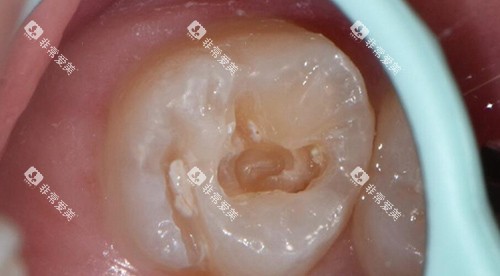

| 根管治疗 | 1200 |